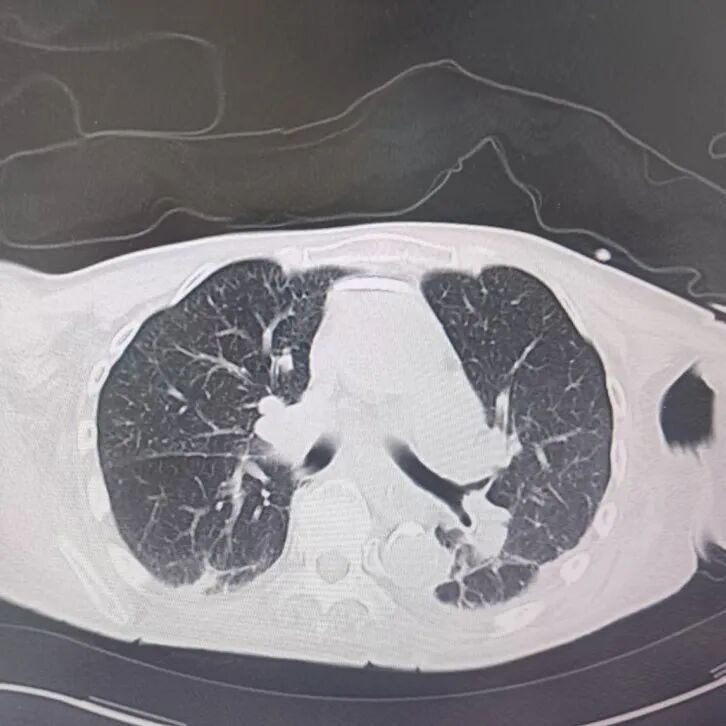

引言 / / Introduction 年近8旬的陳阿姨(化名)因腦梗長(zhǎng)期癱瘓?jiān)诖?,康?fù)期間突然高燒不退,體溫升至39℃,在抗感染過(guò)程中,她并發(fā)高滲性脫水,病情急劇惡化,被緊急送入ICU。此時(shí),她已氣管切開(kāi),依靠呼吸機(jī)維持呼吸,并伴有低蛋白血癥、低鉀高鈉血癥及房顫等多種危重情況,命懸一線! PART. 01 多重泛耐藥菌疊加大量基礎(chǔ)病 治療陷入“死胡同” 呼吸與危重癥醫(yī)學(xué)科及ICU通力協(xié)作,穩(wěn)住患者生命體征。治療過(guò)程中,進(jìn)一步的病原學(xué)檢查結(jié)果令人心驚:陳阿姨的肺部遭遇多種“超級(jí)細(xì)菌”混合侵襲,包括銅綠假單胞菌、鮑曼不動(dòng)桿菌、嗜麥芽窄食單胞菌、金黃色葡萄球菌、木糖氧化無(wú)色桿菌、粘質(zhì)沙雷菌等高度耐藥菌,堪稱(chēng)耐藥菌“大本營(yíng)”。這些細(xì)菌對(duì)常用抗生素幾乎全部耐藥,治療難度高,死亡率高。 治療前患者肺部影像 PART. 02 多學(xué)科強(qiáng)強(qiáng)聯(lián)手 量身定制攻堅(jiān)方案 面對(duì)無(wú)藥可用的困境,呼吸科沒(méi)有放棄!宋剛主任帶領(lǐng)團(tuán)隊(duì)聯(lián)合藥學(xué)部、檢驗(yàn)科、重癥醫(yī)學(xué)科成立多學(xué)科治療組,根據(jù)患者身體情況實(shí)時(shí)調(diào)整用藥,逐一攻破耐藥菌。這場(chǎng)與“超級(jí)細(xì)菌”的拉鋸戰(zhàn)持續(xù)了30多個(gè)日夜。 在醫(yī)護(hù)日夜堅(jiān)守和家屬全力配合下,陳阿姨的感染終于被遏制:高燒退了,肺部陰影消散了!就在即將宣告勝利時(shí),又發(fā)現(xiàn)她存在泌尿感染問(wèn)題,隨即轉(zhuǎn)入泌尿外科協(xié)同治療。當(dāng)宋主任回訪時(shí),看到陳阿姨精神煥發(fā)、體溫平穩(wěn),所有參與救治的人都感慨萬(wàn)分!這場(chǎng)救治,正是呼吸與危重癥醫(yī)學(xué)科攻堅(jiān)耐藥菌硬實(shí)力的生動(dòng)體現(xiàn)! 治療后患者肺部影像 從“無(wú)藥可用”到“絕處逢生”,此次成功救治,集中體現(xiàn)了呼吸與危重癥醫(yī)學(xué)科以耐藥菌精準(zhǔn)診治為核心的學(xué)科特色與技術(shù)優(yōu)勢(shì)。面對(duì)一次次的嚴(yán)峻挑戰(zhàn),科室始終秉持“生命至上、知難而進(jìn)”的信念,以多學(xué)科協(xié)作為平臺(tái),憑借個(gè)體化精準(zhǔn)用藥策略,為患者尋找生機(jī),為更多陷入困境的患者和家庭帶去了實(shí)實(shí)在在的希望。 PART. 03 人民醫(yī)院 人民名醫(yī) 宋剛 主任醫(yī)師 ·葫蘆島市第二人民醫(yī)院呼吸與危重癥醫(yī)學(xué)科主任 ·遼寧省生命科學(xué)學(xué)會(huì)東北呼吸與危重癥醫(yī)學(xué)(PCCM)分會(huì)遼寧省基層委員會(huì)副主任委員 ·遼寧省細(xì)胞生物學(xué)學(xué)會(huì)放射粒子治療專(zhuān)業(yè)委員會(huì)理事 ·遼寧省抗擊新冠肺炎疫情先進(jìn)個(gè)人 ·葫蘆島市勞動(dòng)鑒定委員會(huì)專(zhuān)家?guī)斐蓡T ·葫蘆島市醫(yī)學(xué)會(huì)呼吸內(nèi)科學(xué)分會(huì)第三屆委員會(huì)副主任委員 專(zhuān)業(yè)特色:擅長(zhǎng)呼吸系統(tǒng)疑難及急危重患者的救治,如急慢性支氣管炎、支氣管哮喘、慢性阻塞性肺疾病、肺炎、肺栓塞、肺癌、間質(zhì)性肺疾病、睡眠呼吸暫停綜合征等,尤其擅長(zhǎng)有創(chuàng)無(wú)創(chuàng)機(jī)械通氣、支氣管鏡下相關(guān)檢查及治療(TBNA、氣道支架置入術(shù)、球囊擴(kuò)張等)、全肺灌洗術(shù)等領(lǐng)先技術(shù),發(fā)表國(guó)家級(jí)期刊多篇。